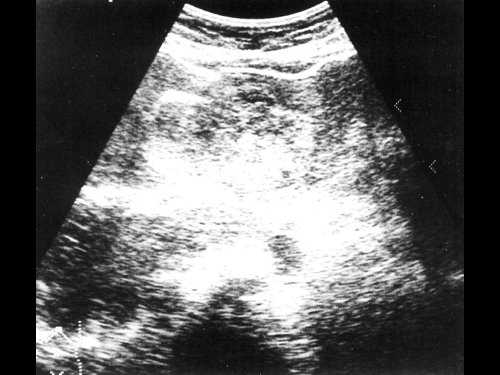

Женщина 50 лет, госпитализирована с болями в верхнем правом квадранте живота. Ультразвуковое исследование органов брюшной полости было проведено в день поступления (рис. 1а, б).

Рис. 1. УЗИ печени.

a) На эхограмме в правой доле печени видны два гиперэхогенных образования с четкими контурами (3,0x1,5 см, 2,5x1,5 см).

б) На эхограмме в левой доле печени видно большое гетерогенное образование (5.0x4.0 см), имеющее дольчатое строение.

Диагноз - множественная гемангиома печени

В нашем случае при ультразвуковом исследовании брюшной полости выявлено атипичное строение гемангиомы, динамическая компьютерная томография указывает на типичную гемангиому (рис. 2а, б). При этом важно знать, что только приблизительно в 54% случаев у больных с гемангиомами имеет место характерная перфузия с центростремительным усилением и поздним заполнением [20]. Однако в связи с тем, что этот тип усиления встречается только у 1,6% первичных и вторичных злокачественных опухолей печени, определение структуры данного усиления позволяет уверенно дифференцировать гемангиомы от злокачественных печеночных опухолей [20].